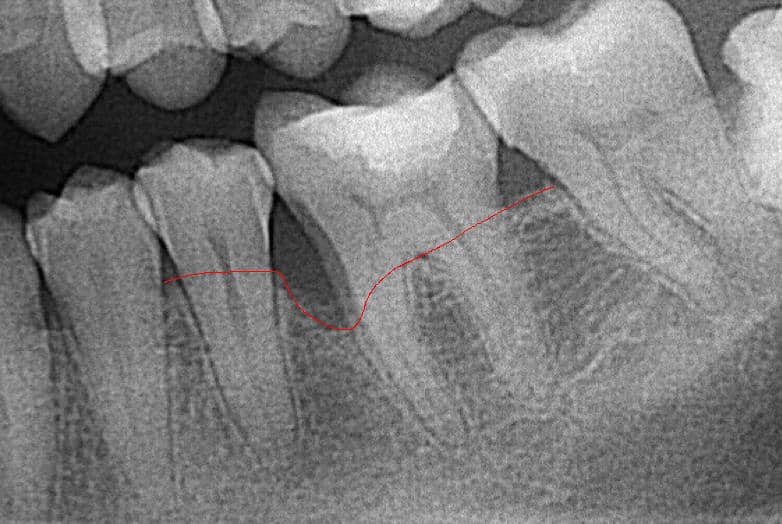

The image below clearly shows bone loss.